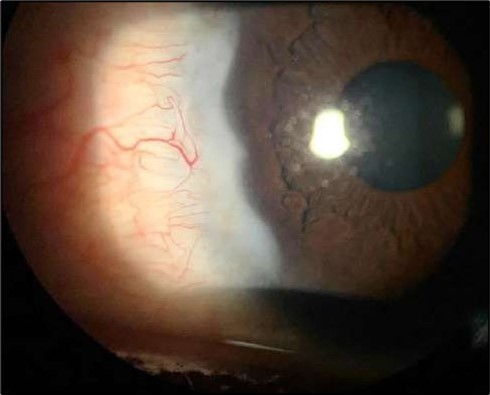

At six-months follow-up post-resection, the ulcer showed progressive epithelialization with no recurrence. Oral prednisolone was gradually tapered and stopped. The patient remains under regular ophthalmology follow-up with stable ocular findings Figure 6.

Figure 6.Six-month follow-up image showing a stable ocular surface, and absence of ulcer recurrence. The cornea appears clear centrally, with stromal scarring limited to the periphery.

Long-term follow-up is essential as Mooren’s ulcer may recur even after resolution. In a large cohort, cumulative recurrence risk was 10.4% at 6 months, 17.1% at 12 months, 22.5% at 24 months, 27.2% at 36 months, and 28.6% at 48 months 33. Regular monitoring allows early detection and timely initiation and adjustment of medical or surgical therapy.